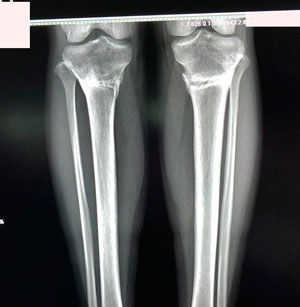

Исходник - 27 лет. Якутия.

Дата операции - 12.07.2019г.

Ротация справа.